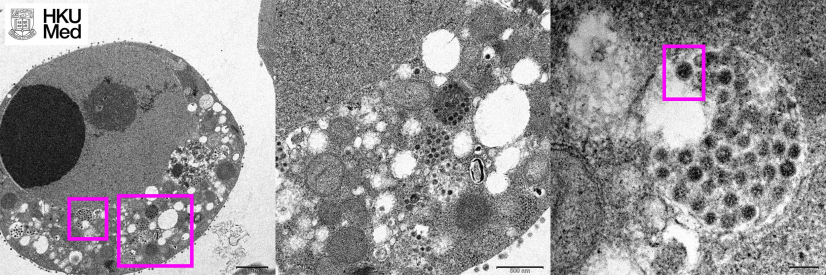

(Left) Low magnification electron micrograph of a Vero (monkey kidney) cell 24 hours after infection with the Omicron variant of SARS-CoV-2. The boxes show clusters of viral particles in the cytoplasm.

(Centre) High magnification electron micrograph of the larger box in the left panel showing aggregates of viral particles in vesicles and on the surface of the cell.

(Right) High magnification electron micrograph of the smaller box in the left panel showing large aggregates of viral particles with spikes (box) in membrane bound vesicles.

Photo credit: Professor John Nicholls, Clinical Professor of Department of Pathology, HKUMed; Professors Malik Peiris, Tam Wah-Ching Professor in Medical Science and Chair Professor of Virology, School of Public Health, HKUMed; Professor Leo Poon Lit-man, Professor and Head of Division of Public Health Laboratory Sciences, School of Public Health, HKUMed; and Electron Microscope Unit, HKU.